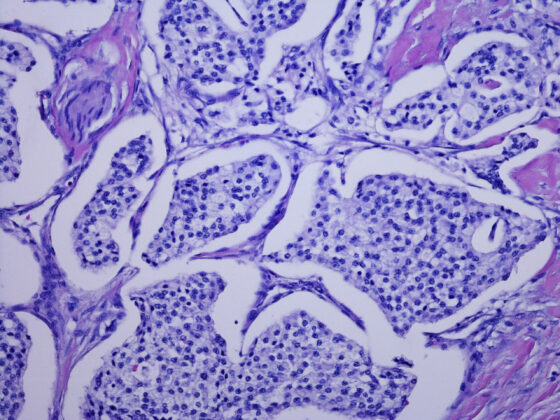

• PancNEN, PancNET & PancNEC

Neuroendokrine Tumoren des Pankreas